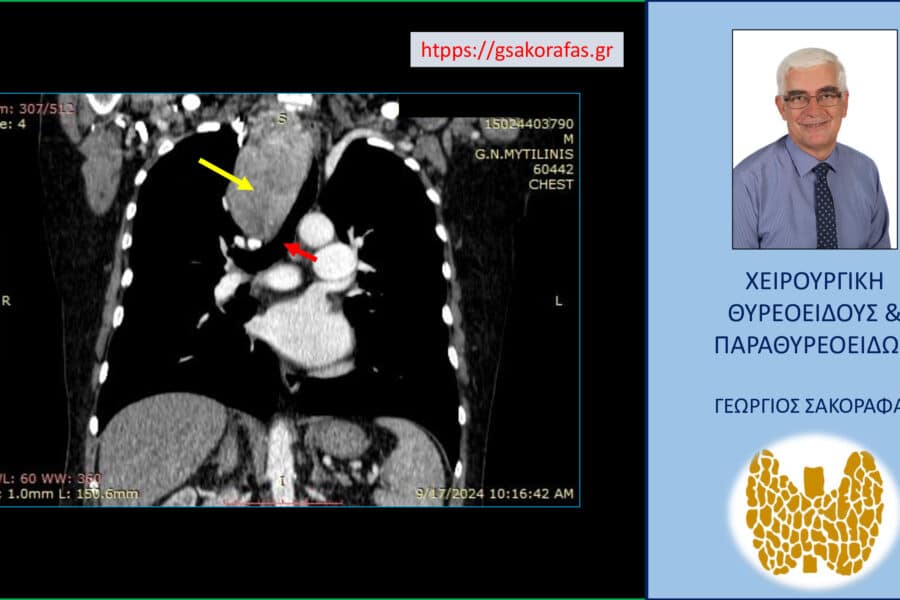

Όζοι θυρεοειδούς και συμπληρωματική θυρεοειδεκτομή (completion thyroidectomy) – με αφορμή ασθενή μας Παρουσίαση ασθενούς Αιτία…